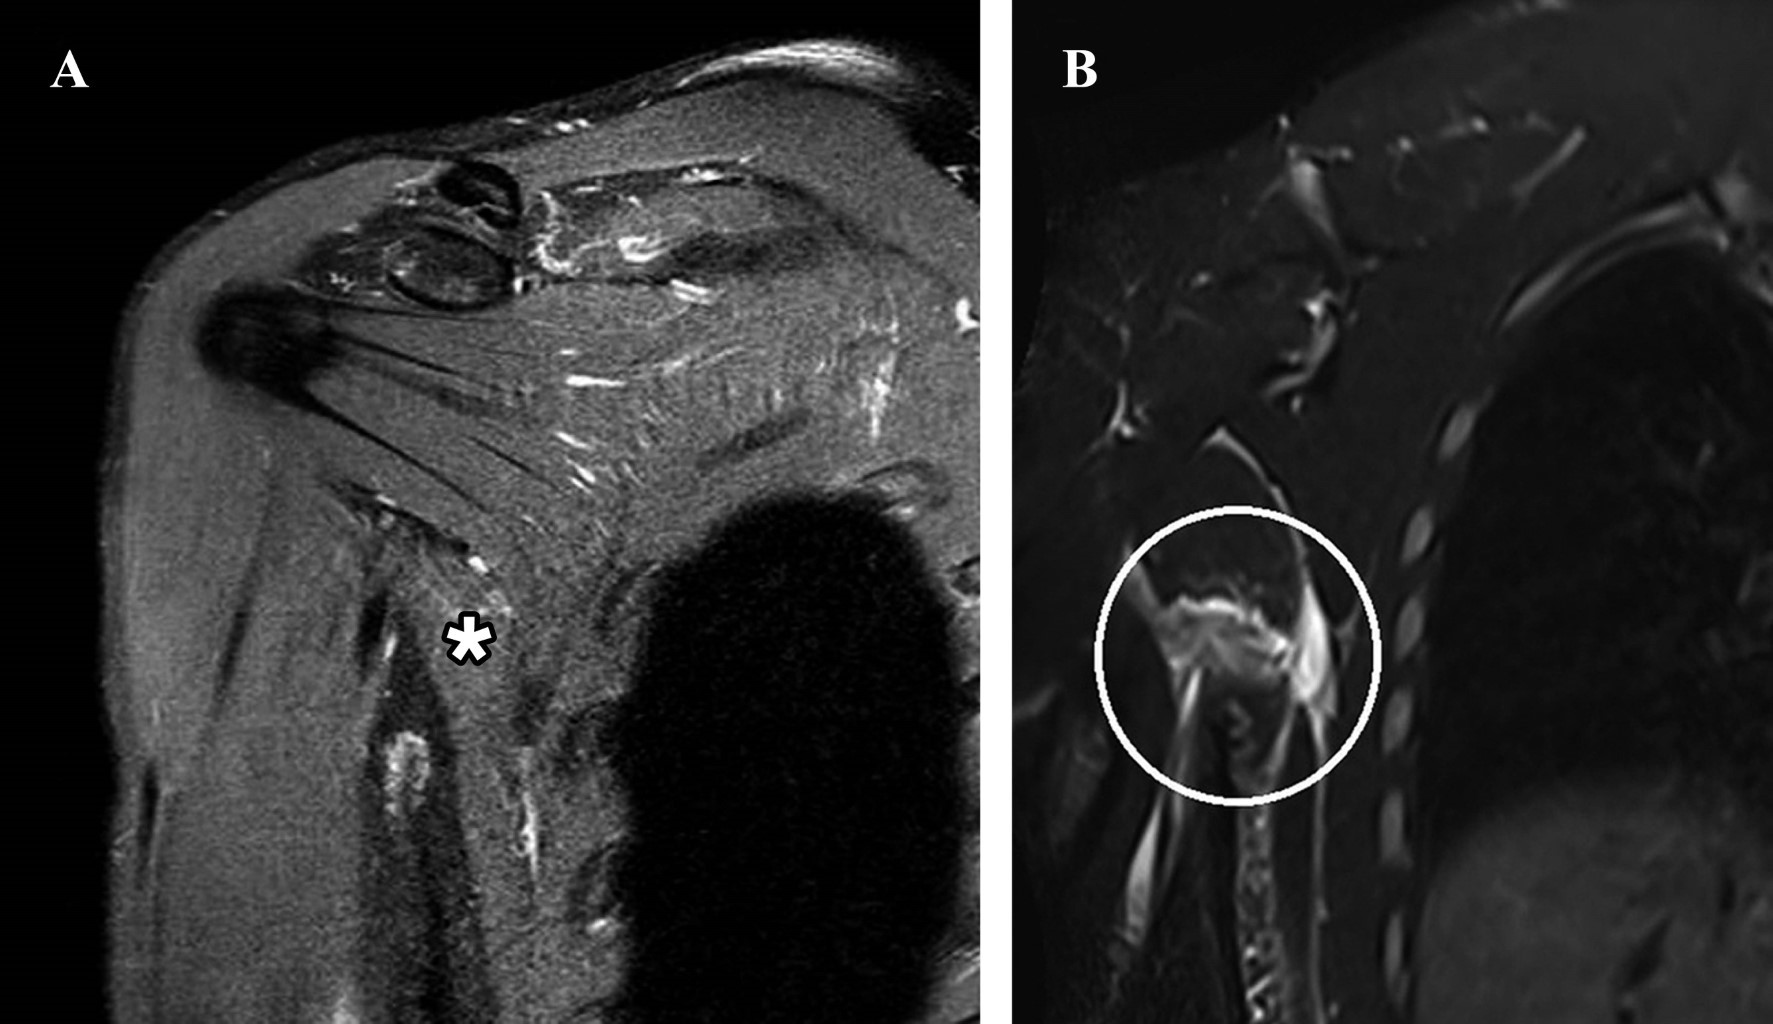

La rotura del músculo redondo mayor es una afección muy conocida en actividades deportivas como el béisbol, el hockey y el tenis. No existe un consenso real en la literatura sobre el tratamiento, y los enfoques varían entre métodos funcionales y quirúrgicos. Si bien el tratamiento funcional parece ser una opción viable, falta evidencia que indique una mejora significativa en la fuerza de rotación medial después de dicho tratamiento. Presentamos a un hombre de 30 años con dolor debajo de la axila derecha durante los últimos 10 días, atribuido al entrenamiento de jiu-jitsu, que reveló un desgarro completo de la unión musculotendinosa del redondo mayor y un desgarro de inserción parcial (aproximadamente el 75% de espesor) de los tendones supraespinoso e infraespinoso, junto con atrofia en la transición musculotendinosa del pectoral mayor. El paciente fue tratado con medicación analgésica, acompañada de tratamiento fisioterapéutico que incluyó electrotermofototerapia, terapia con láser/LED, terapia manual y un régimen de ejercicio estructurado durante 14 semanas, reintroduciendo gradualmente el entrenamiento deportivo específico.

Figura 1